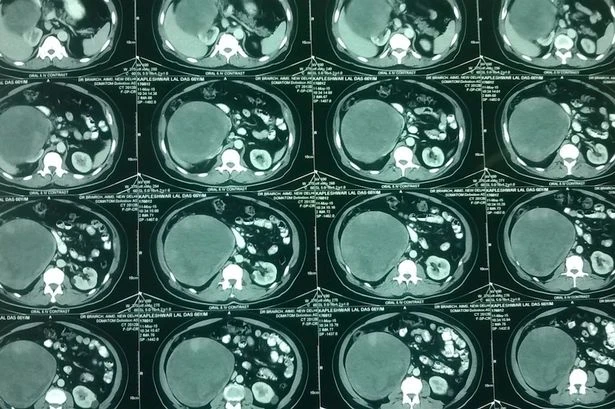

Hình ảnh chụp CT cho thấy khối u trong ổ bụng kích cỡ bằng quả dưa hấu.